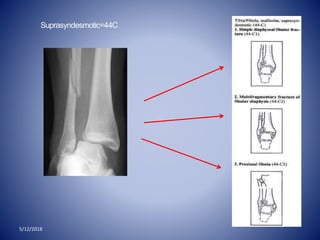

Suprasyndesmotic=44C